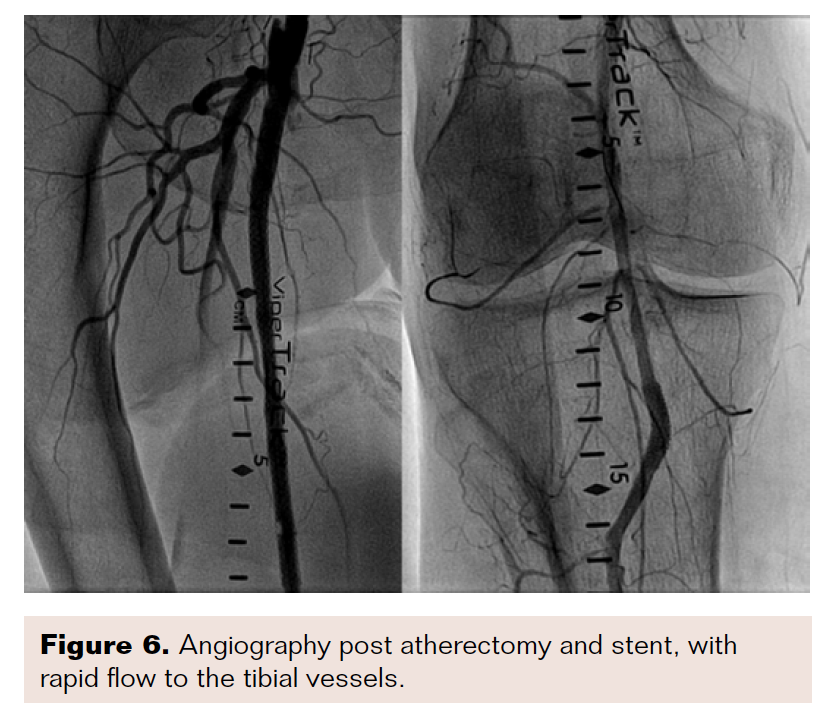

After approximately three hours of acoustic pulse thrombolysis therapy, the patient’s ischemic pain had worsened, and no signs of revascularization were seen. The decision was made to bring the patient back for a repeat angiogram. Subsequent angiography demonstrated no improvement in the thrombus burden and it was decided to proceed with intervention at the native right SFA chronic total occlusion. We used a Quick-Cross catheter (Philips) and V-18 wire (Boston Scientific) and unsuccessfully tried to cross the chronic total occlusion antegrade. We subsequently went through the graft and came retrograde through the distal anastomotic site. We crossed into the common femoral artery and the wire was externalized through the sheath. Atherectomy and stent placement were performed to establish brisk flow to the foot (Figures 5-6).